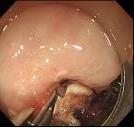

• 电子胃镜联合实验室指标检测在胃癌诊断中的价值及其与临床病理特征的关系

2025, 31(12):49-55. DOI: 10.12235/E20240712

摘要 (65) HTML (26) PDF 718.76 K (63) 评论 (0) 收藏

摘要:目的 探究电子胃镜联合实验室指标[血清糖类抗原724(CA724)、糖类抗原19-9(CA19-9)、微RNA-183(miRNA-183)和微RNA-144(miRNA-144)]检测在胃癌诊断中的价值及其与临床病理特征的关系。方法 选取2022年12月-2023年12月经病理检查确诊的122例胃癌患者作为A组(2022年12月-2023年12月该院收治),纳入该院同期收治的130例胃部良性肿瘤患者作为B组。所有患者在病理检查确诊前均先行电子胃镜检查,比较两组患者电子胃镜检查阳性率、血清CA724、CA19-9、miRNA-183和miRNA-144水平,并分析其对胃癌的诊断价值,比较不同病理特征胃癌患者电子胃镜检查阳性率及血清指标水平。结果 A组电子胃镜检查阳性率、血清CA724、CA19-9和miRNA-183水平高于B组,血清miRNA-144水平低于B组,差异均有统计学意义(P < 0.05)。与单独诊断相比,五者联合诊断胃癌的曲线下面积(AUC)更高,差异有统计学意义(P < 0.05)。不同分化程度、淋巴结转移情况和TNM分期患者电子胃镜检查阳性率、血清CA724、CA19-9、miRNA-183和miRNA-144水平比较,差异均有统计学意义(P < 0.05)。结论 电子胃镜检查在诊断胃癌及评估其病理特征方面,具有较好的应用效果,相关实验室指标(血清CA724、CA19-9、miRNA-183和miRNA-144)与胃癌的发生及病理特征密切相关,五者联合检测,可提高对胃癌的诊断效能。